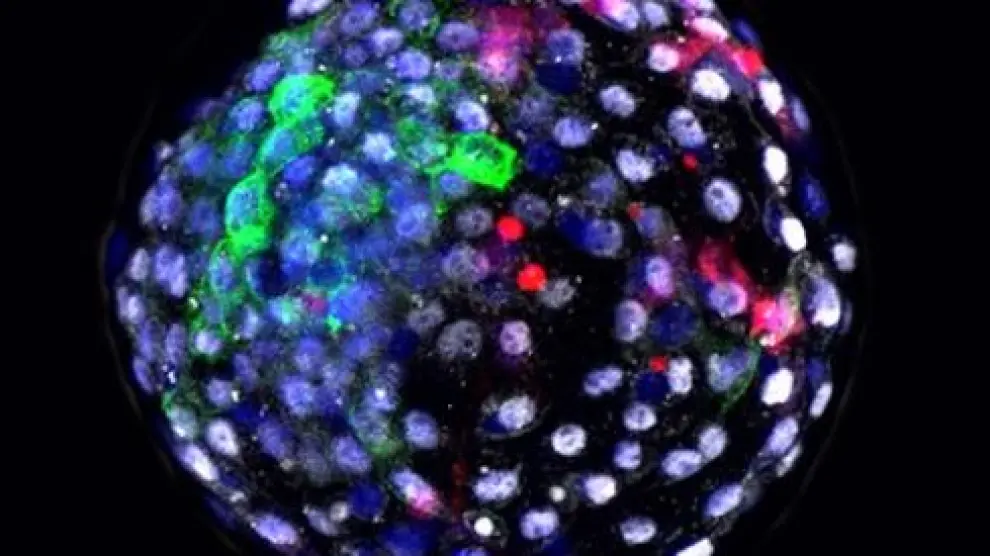

En el estudio que ahora se publica en 'Cell', los investigadores etiquetaron células madre reprogramadas pluripotentes humanas hiPCs (células que son capaces de convertirse en todos los tipos de células del cuerpo) con una proteína fluorescente, e insertaron estas células marcadas en embriones de macacos en el laboratorio.

En el trabajo actual, el experimento finalizó 19 días después de la inyección de las células humanas y, mediante estudios de inmunofluorescencia, los investigadores observaron que las células madre humanas sobrevivieron y se integraron en el embrión de macaco con mejor eficiencia relativa que en los experimentos previos llevados a cabo en cerdos.

Para identificar las vías de comunicación molecular entre las células de las dos especies en el estudio actual, se analizó el transcriptoma de la quimera generada, o lo que es lo mismo, se hizo una lectura de qué genes y qué moléculas estaban activos. Observaron que las células de las quimeras tenían distintos perfiles transcriptómicos que los controles y detectaron que se habían activado varias vías de comunicación.